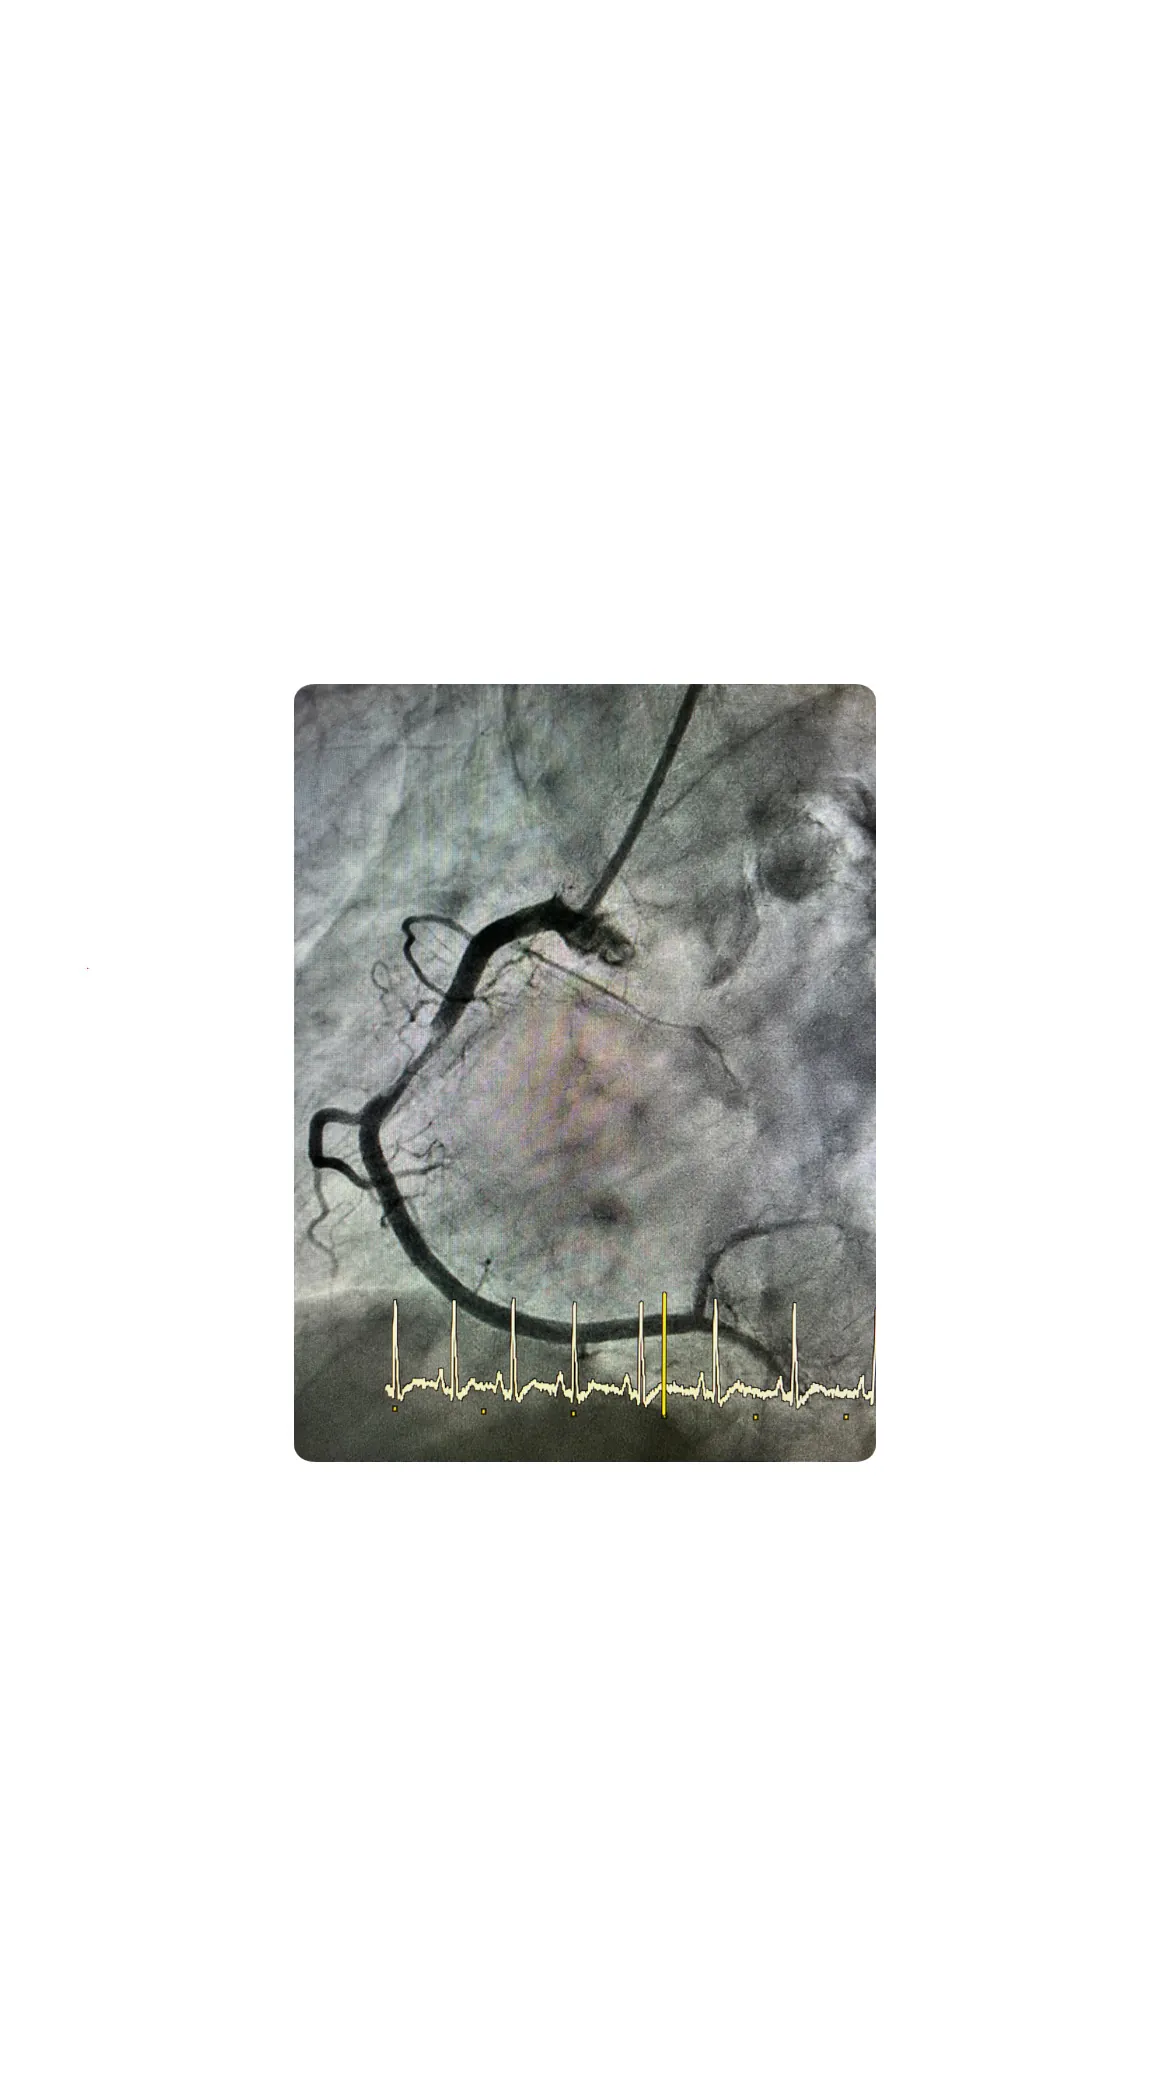

Ablación septal: cuándo se plantea y en qué consiste

Una mirada detallada a este procedimiento cardiológico y sus indicaciones